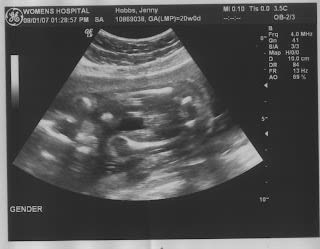

I had my ultrasound today and the technician wasn't sure of the gender of our baby but she decided that it's probably a boy... here are some pictures of our cute little Mario.

We are so happy and excited about our little Mario.

Mouth closed

Mouth Opened

Little foot

Little...boy part